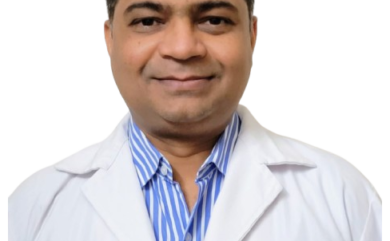

Best Radiologist in Dehradun | Dr. Ramesh Kumar Pandey | Interventional Radiologist Dehradun

Best Radiologist in Dehradun | Dr. Ramesh Kumar Pandey |…